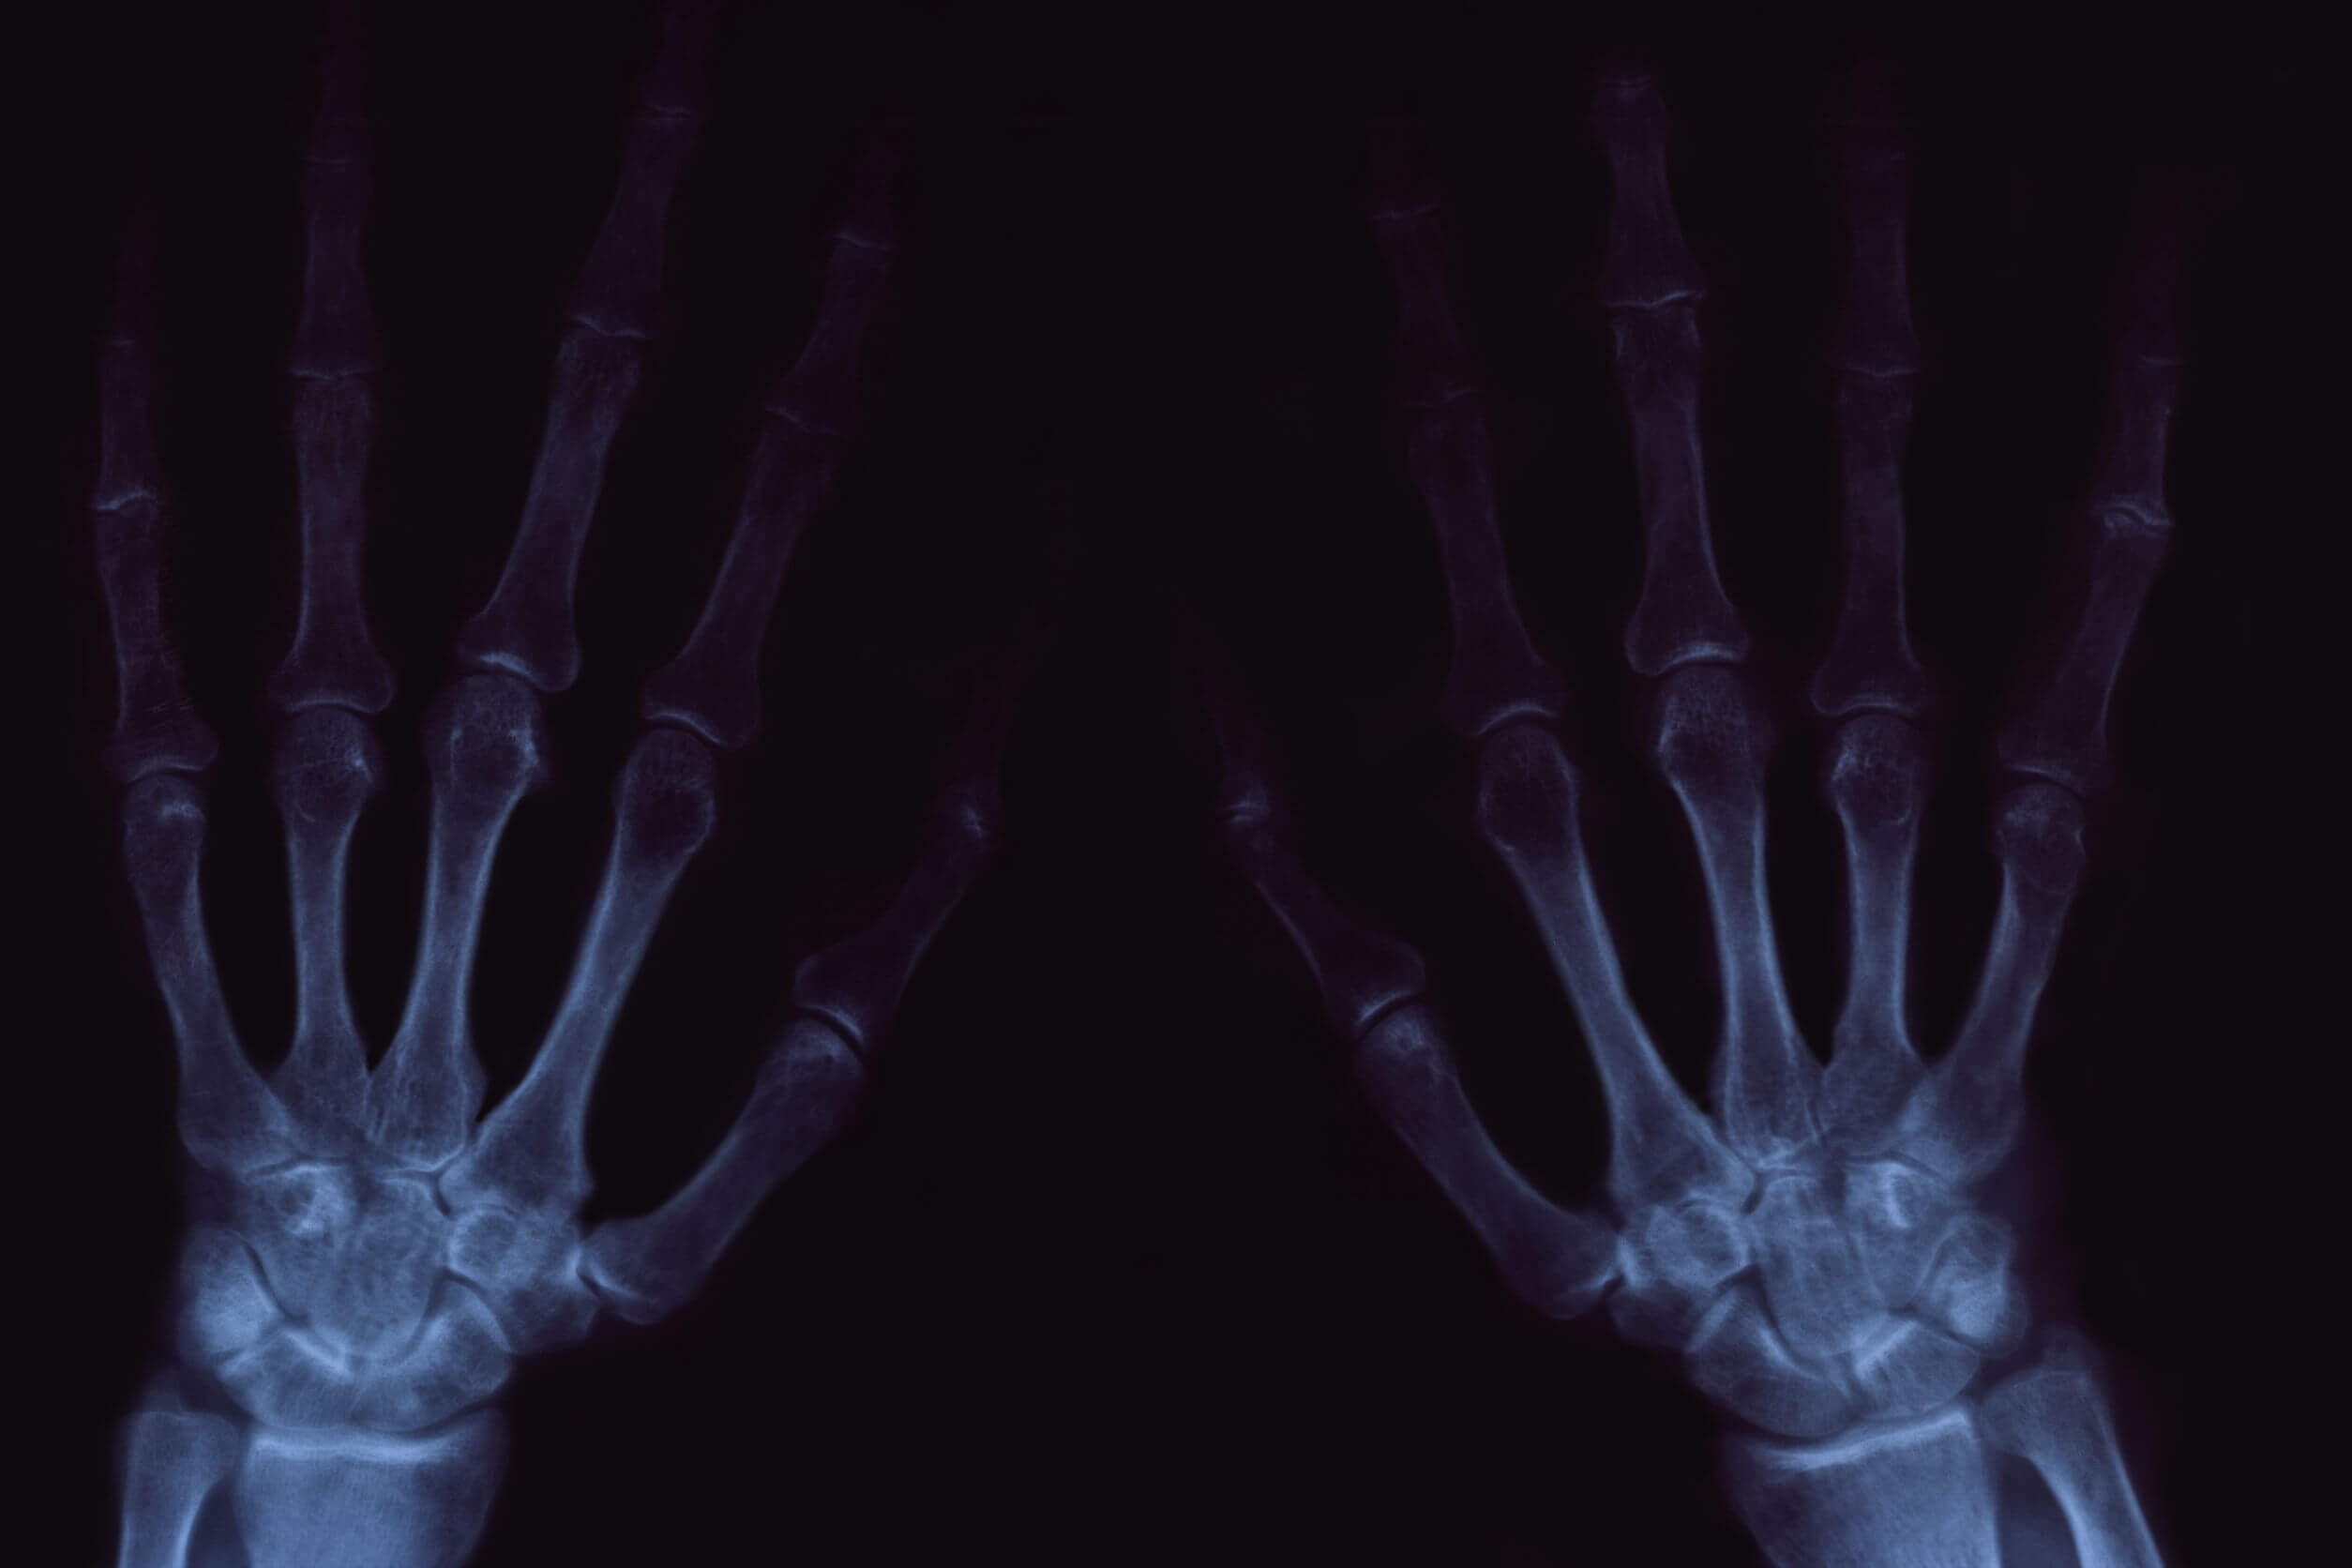

Synovitis en kraken van de gewrichten

Dit is de ontsteking van het synoviale membraan. Het kan geïsoleerd voorkomen of als gevolg van andere ontstekingsaandoeningen in hetzelfde gebied, zoals reumatoïde artritis. Dit wordt gekenmerkt door het optreden van abrupte pijn en volumetoename in het aangetaste gewricht.

Andere aandoeningen die gepaard kunnen gaan met synovitis zijn tendinitis (die samen bekend staan als tenosynovitis), jicht, lupus en dezelfde artrose die we in de vorige paragraaf hebben besproken.